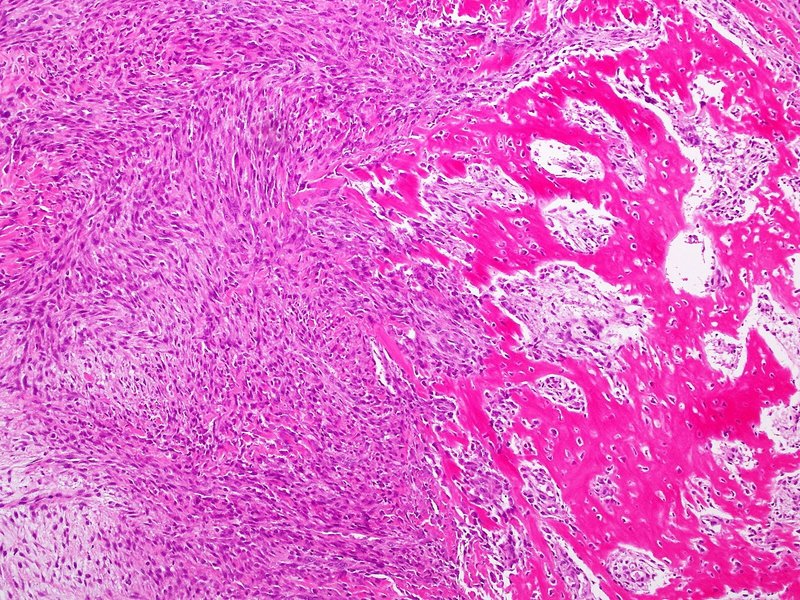

結節性筋膜炎の組織学

組織学とは、腫瘍内の特定の種類の細胞を指します。これらは、腫瘍組織を顕微鏡で観察することで確認できます。悪性腫瘍と結節性筋膜炎には、同様の細胞集団が存在することがあります。

顕微鏡で観察すると、結節性筋膜炎組織の細胞は次のような緩い束となって浮遊しています。

- 線維芽細胞、結合組織に見られる紡錘形の細胞

- 筋線維芽細胞、線維芽細胞と平滑筋組織の間にある大きな細胞

細胞束は粘液様間質と呼ばれる粘液状のマトリックス内を移動します。

以下は結節性筋膜炎組織の他の特徴です。

- 細胞の束は、移動するときに「S」字または「C」字の形を形成し、場合によっては側転の形を形成します。

- 細胞は羽毛のような外観をしており、組織に穴や裂け目ができています。

- 細胞分裂中に細胞の染色体が見えます。

- 染色体物質 (クロマチン) は細かく、淡く、均一に見えます。

- 細胞はその形状を変えません(非多形性)。

- 細胞は高い速度で分裂 (有糸分裂) します。

研究者は細胞を染色して、その構造と反応性を調べることがあります。結節性筋膜炎の細胞特性の一部は、腫瘍の位置に応じて変化する場合があります。

診断には組織像が重要です。対照的に、悪性肉腫では通常、次のような症状が起こります。

- 4センチメートルより大きい

- 形状が変化する細胞(多形性)を持っています

- 粗くて粒状で不規則な染色体物質を持っています

- 細胞分裂に異常がある